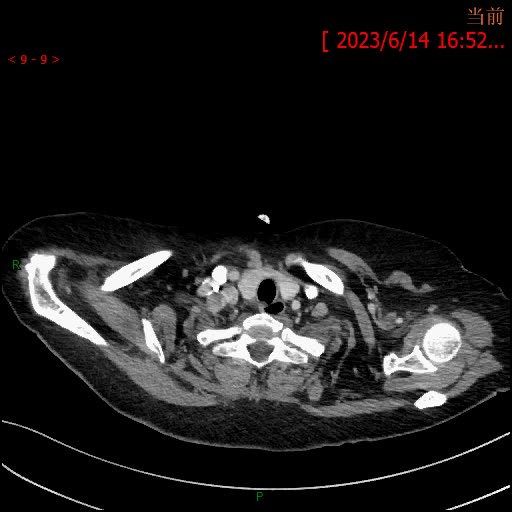

3天后增强检查视频: